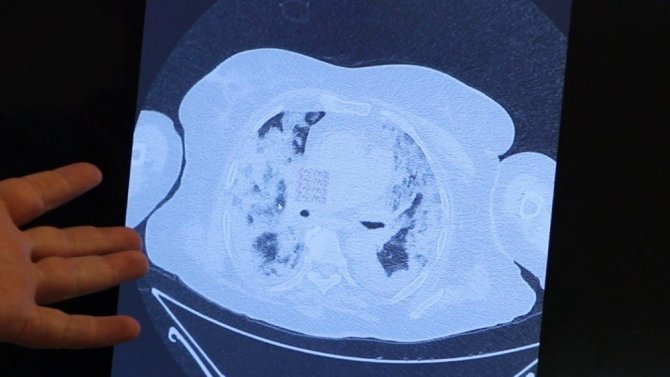

Farklı aileden yaşları yüksek olan 4 kişinin akciğer tomografilerini de inceleyen Prof. Dr. Şevket Özkaya genellikle hastaların akciğerlerinin hava yerine bir sıvı ile dolduğunu belirterek, "Biz mart-nisan aylarından sonra Türkiye'de korona virüs vakalarının ilk olduğu dönemlerde genelde her ailede bir kişinin enfekte olduğunu görüyorduk. Onu kontrol altına almaya çalışıyorduk. Oysa son 3-4 aydır ailedeki bir kişinin bütün aile fertlerini enfekte ettiğini ve en az 5 ile 10 kişilik bir ailede herkesin enfekte olduğunu görüyoruz. Bu kişilerin en az 1-2 tanesinin özellikle yaşlı kişileri yoğun bakıma düşürecek kadar zatürre olduğunu gördük" dedi.

"Tomografilerde yaygın buzlu camlar ve sıvı"

Farklı ailelerden 4 kişinin akciğer tomografilerine bakan Prof. Dr. Özkaya, "82 yaşındaki 4 çocuğu da korona virüse yakalanmış bir hastanın filmine bakarsak, akciğerlerinde yaygın pnönomoni olduğunu görüyoruz. Bu kişi yoğun bakımda tedavi altına alındı. Artık eskisi gibi ailede tek tük enfektelere bakmıyoruz. Ailenin tamamı enfekte oluyor ve özellikle yaşlıları çok ciddi zatürreye döndürecek klinik durumlarla karşılaşıyoruz. 58 yaşında genç bir annenin akciğerlerine bakıyoruz. 3 çocuğunun hepsi ve eşi de enfekte olmuş. Ailede bir kişi enfekte olunca hepsini enfekte etmiş. Maalesef içlerinde immün direnci en düşük olan ve yaşı en büyük olanın akciğerleri solunum yetmezliğine gidecek şekildedir. Her iki akciğerinde de yaygın infiltrasyonla tedavi veriyoruz. Hasta hayati tehlikeyi atlattı. 63 yaşında bir hastanın akciğerlerini inceliyoruz. 63 yaşındaki bu anne yaşıyor ama bu kişilerinin anneannelerini ve babaannelerini Kovid-19 dolayısıyla kaybettik" diye konuştu.